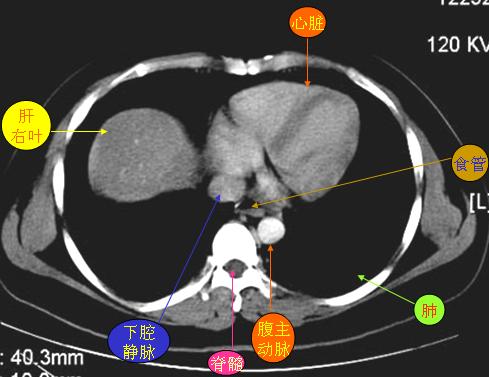

腹部ct解剖与基本病变